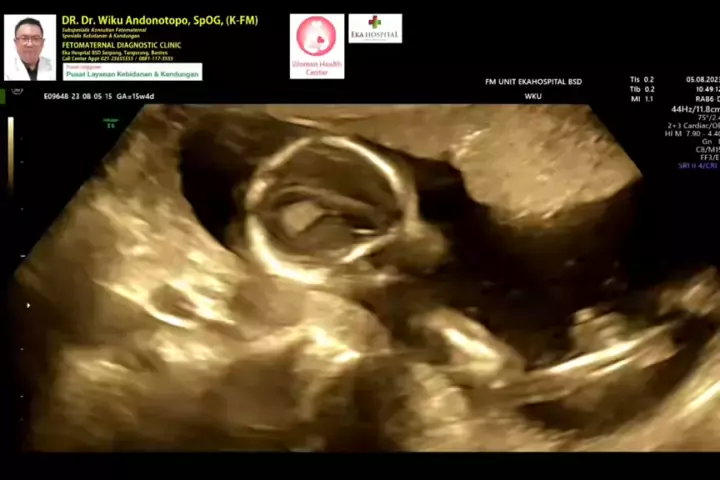

Janin 15 weeks.... #skriningkehamilan #drwikuandonotopo #drwiku_andonotopo #polikandunganekahospitalbsd #ekahospitalbsd #ekahospitalcibubur #ekahospitalpekanbaru #ekahospitalbekasi #rsiafamilypluit #grandfamilypik #usgkehamilansehat #usgkehamilan #usg4d #usg4dimensi #fetomaternal #usgfetomaternal #konsultanfetomaternal #fetomaternalpontianak #fetomaternalekahospitalbsd #fetomaternaljakarta #fetomaternalserpong #fetomaternaltangerang #fetomaternalmedan #fetomaternalpalembang #fetomaternalpadang ...